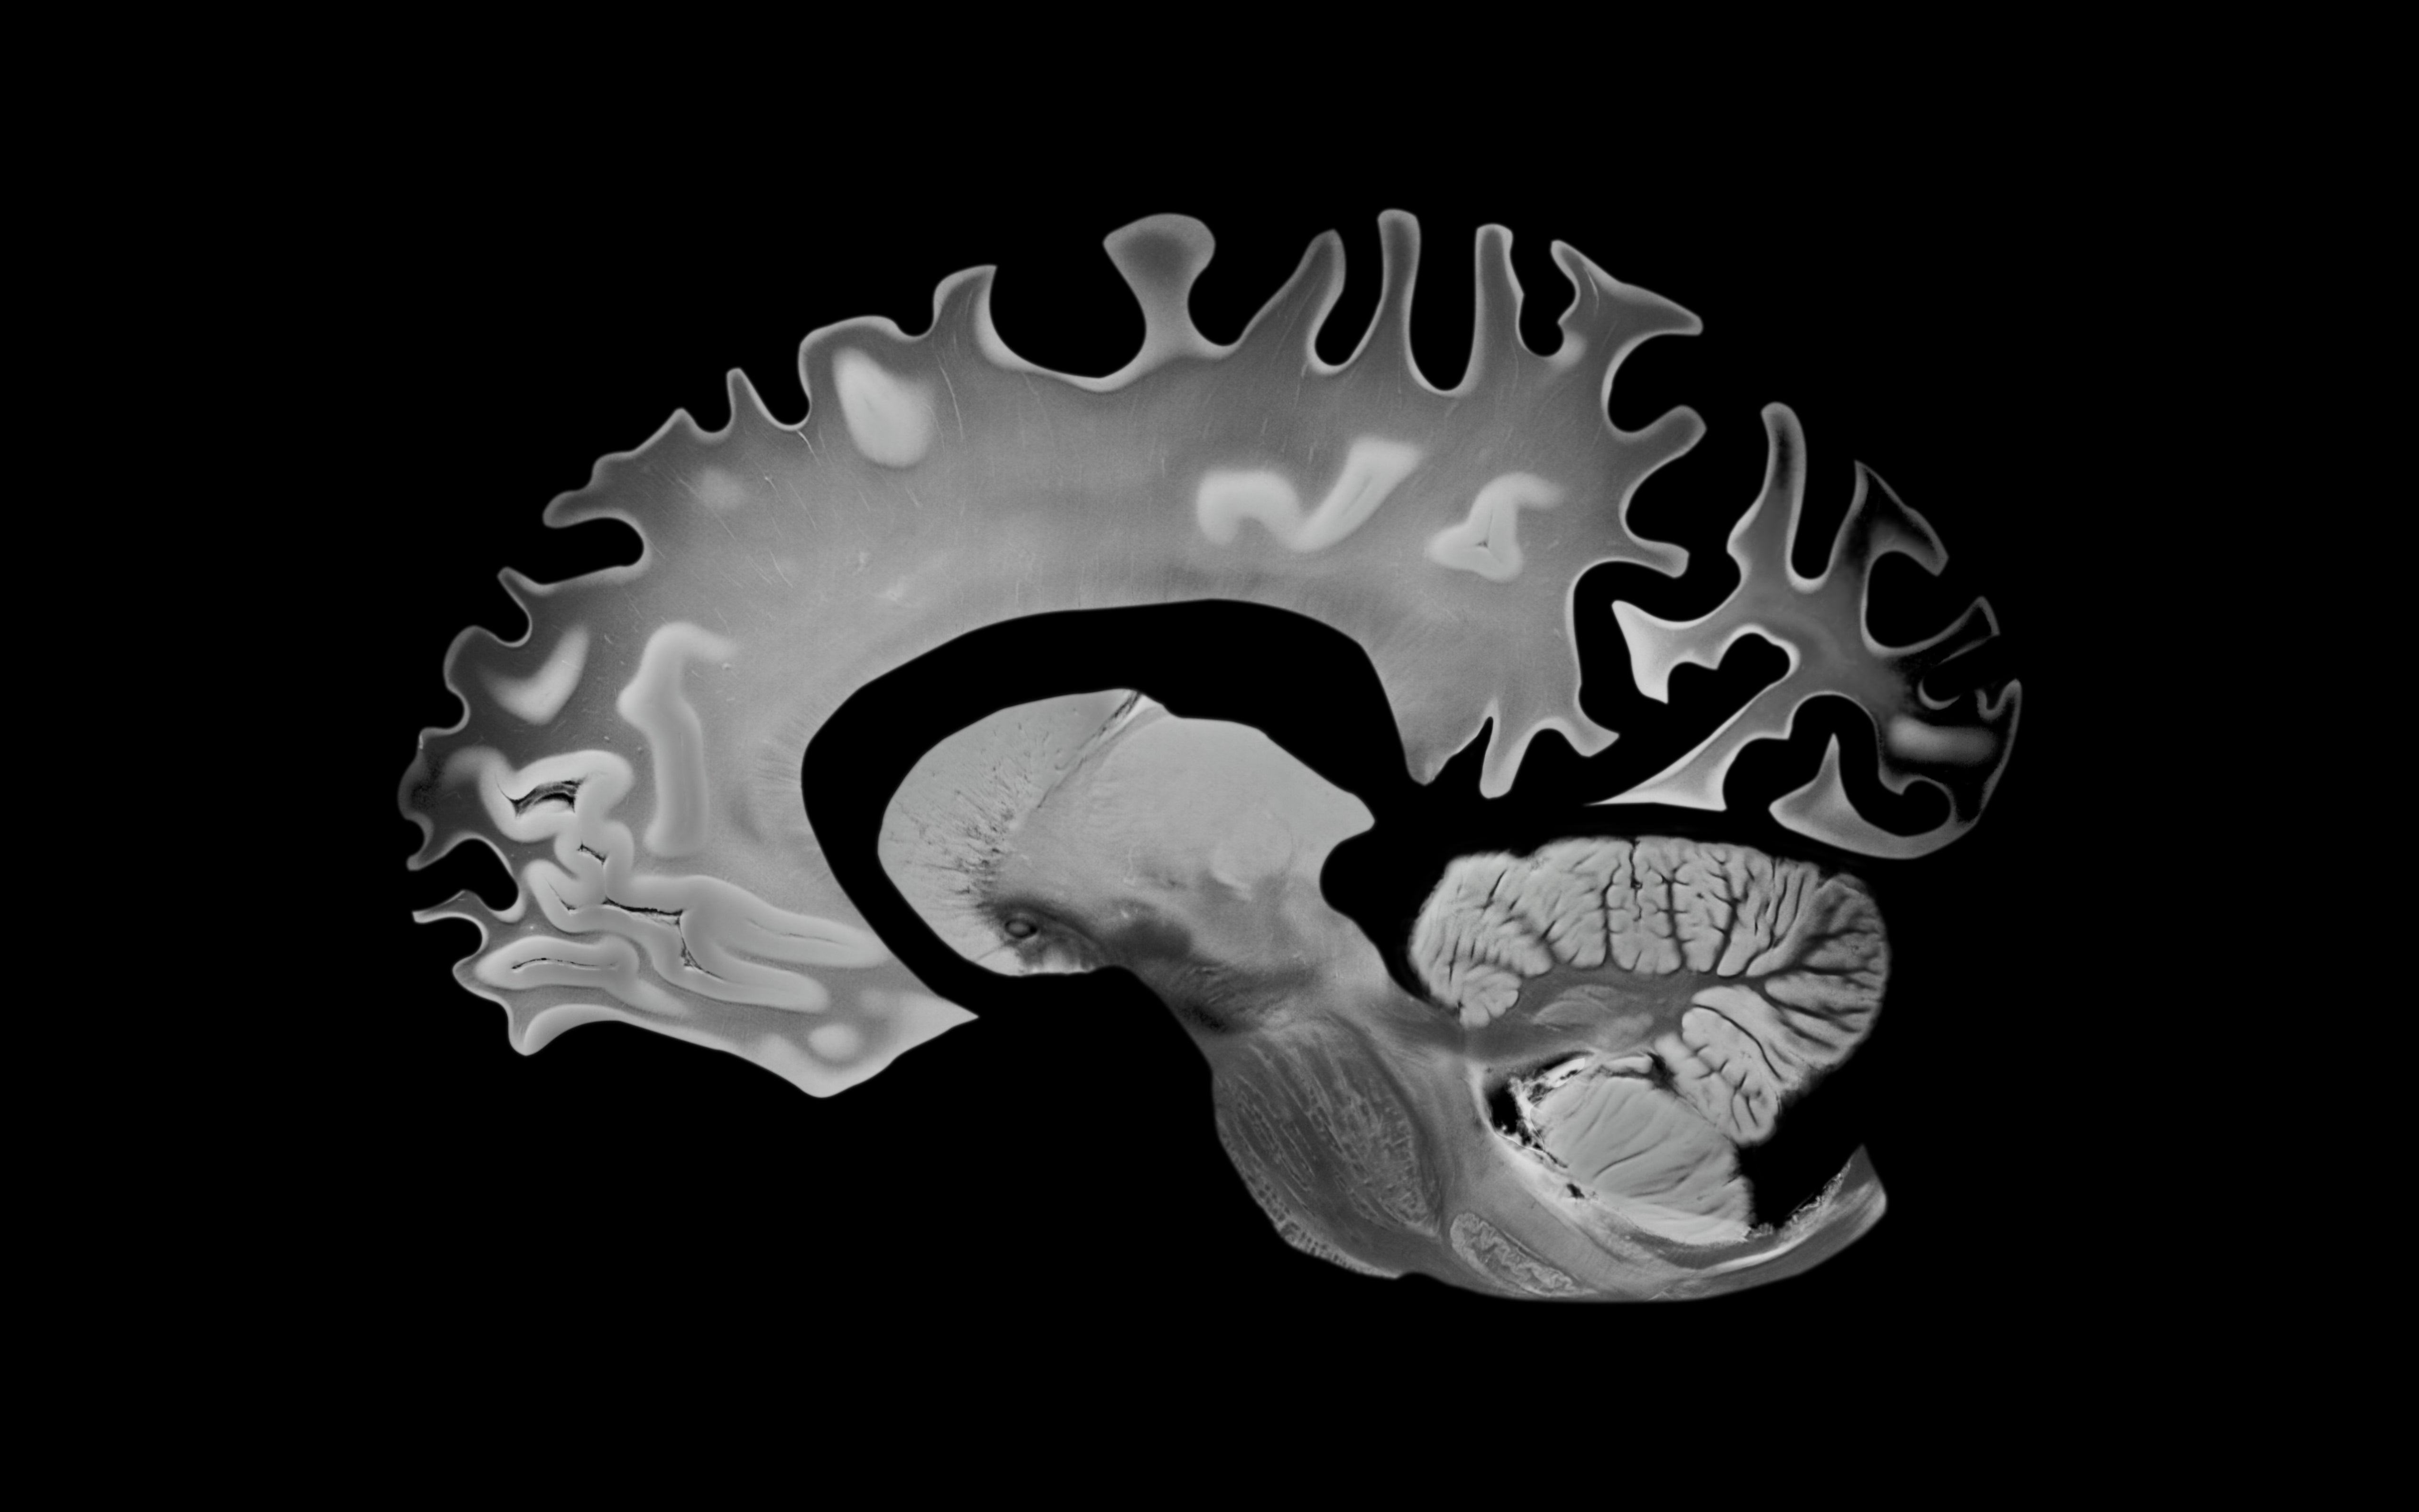

Neurologists Are Opening Up About Sleep Problems That Might Be Warning Signs Of Dementia

Experts reveal which sleep disturbances may signal something deeper, and when you should be concerned. This article originally appeared on HuffPost.